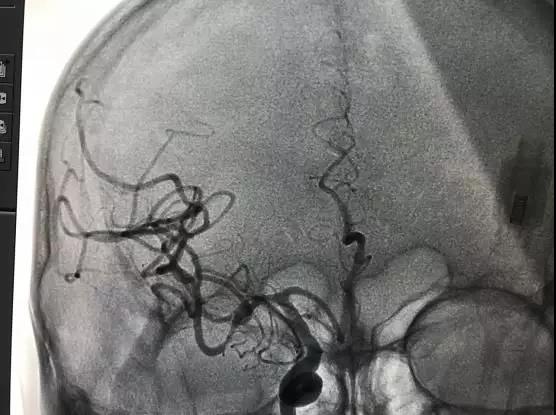

申请成为“卒中中心”和“综合防治卒中中心”的医院,也就成为衡量一家医疗机构卒中综合诊疗救治能力的最直接标准。“综合防治卒中中心”是卒中中心的高级形式,不仅要求医院能够进行急性脑血管疾病的常规治疗,还必须具备高难度的动静脉溶栓、桥接取栓及动脉瘤栓塞等综合救治能力,能够第一时间开通卒中中心转诊患者的绿色通道,医院的科研水平、人才培养也需要达到较高层次。

医院启动“三大中心建设”,正式成立卒中中心。以多学科协作模式为基础,打造了一支由神经内、外科专业力量,联动急诊科、120急救中心、检验科、影像科、药学科、康复科、介入室等多科协作的“脑卒中救治团队”,24小时联动待命。建立起包含急性期救治、早期康复、二级预防、随访宣教等功能于一体的相对独立的学科联合体系,实现了院前院内无缝对接,缩短了脑卒中患者入院检查、治疗的时间,有效降低了脑卒中患者的致残率和死亡率,实现了卒中救治的标准化。

伴随着地图的颁布,我区首例动脉取栓术成功独立完成,术后患者恢复良好。

2020年1月,卒中中心顺利通过山东省卒中中心建设专家委员会评审专家组的现场核查认证,并在全国防治卒中中心300强名单中获综合排名25名; 进入全国防治卒中中心AIS血管内治疗技术50强;进入全国防治卒中中心静脉溶栓技术200强;11月,正式成为国家级“综合防治卒中中心”单位。